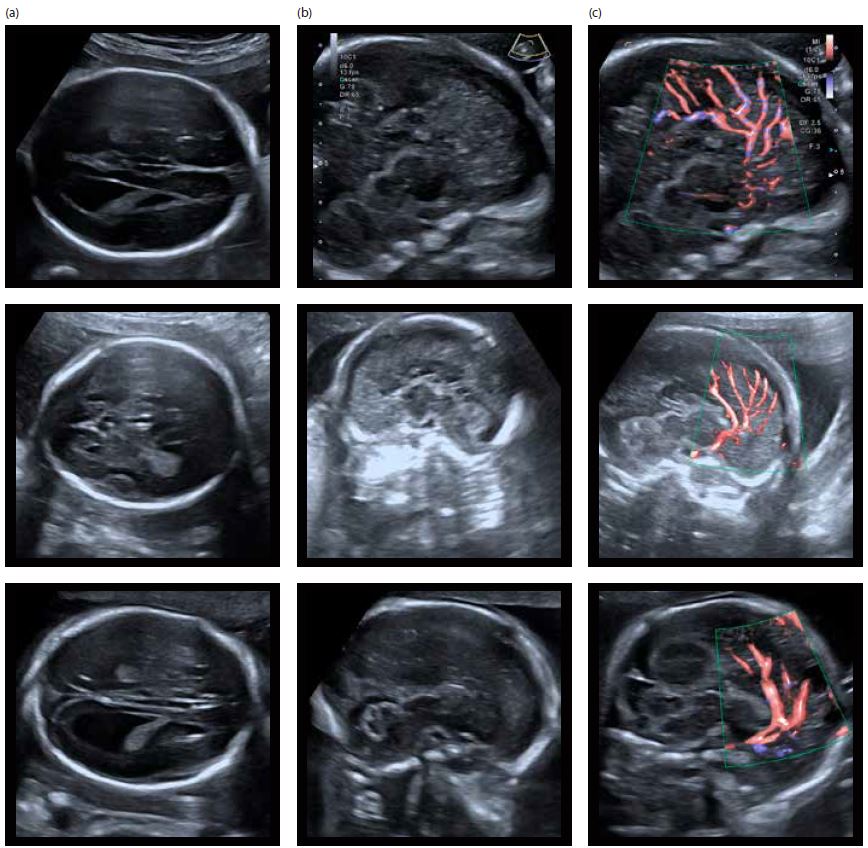

Використання високочастотного конвексного датчика виявилося дуже корисним при дослідженні аномалій мозолистого тіла (повна агенезія, часткова агенезія). Він дозволяє отримати високу деталізацію при дослідженні середньої частини та навколишніх структур головного мозку (паренхіми головного мозку, кори головного мозку) і дає дійсно інформативні зображення (мал. 3 і 4).

Малюнок 3 Три випадки повної агенезії мозолистого тіла; зліва направо:

a) Аксіальні зрізи головного мозку з непрямими ознаками захворювання (відсутність порожнини cavum septum pellucidum, кольпоцефалія)

b) Серединний сагітальний розріз (мозолисте тіло не візуалізується)

c) Відсутність нормального напівкруглого ходу перікаллозальної артерії з променевим розташуванням гілок передньої мозкової артерії (ADF і SMI)